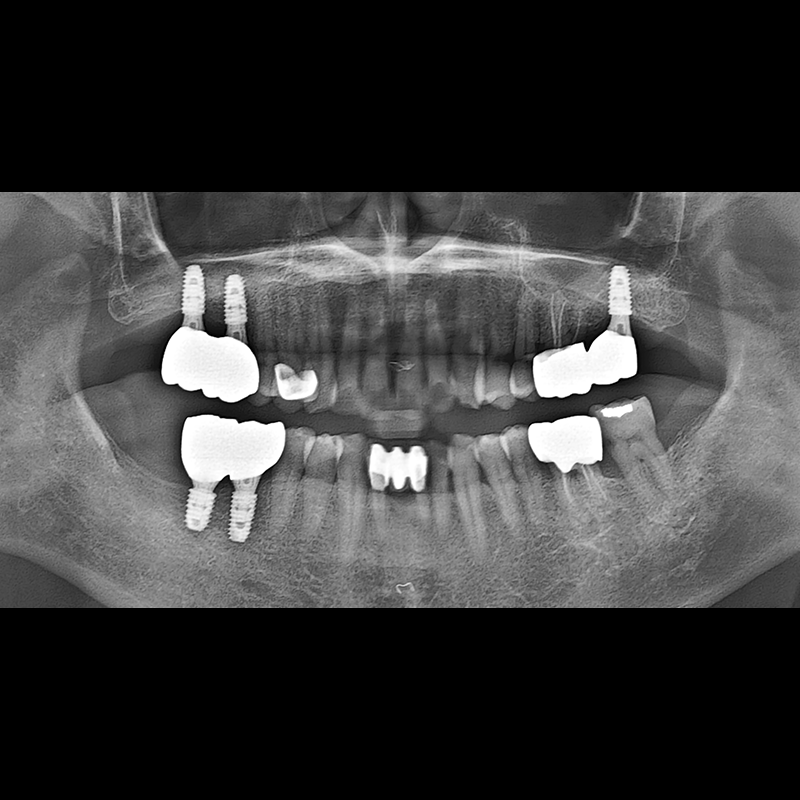

IMPLANT

BEFORE AFTER